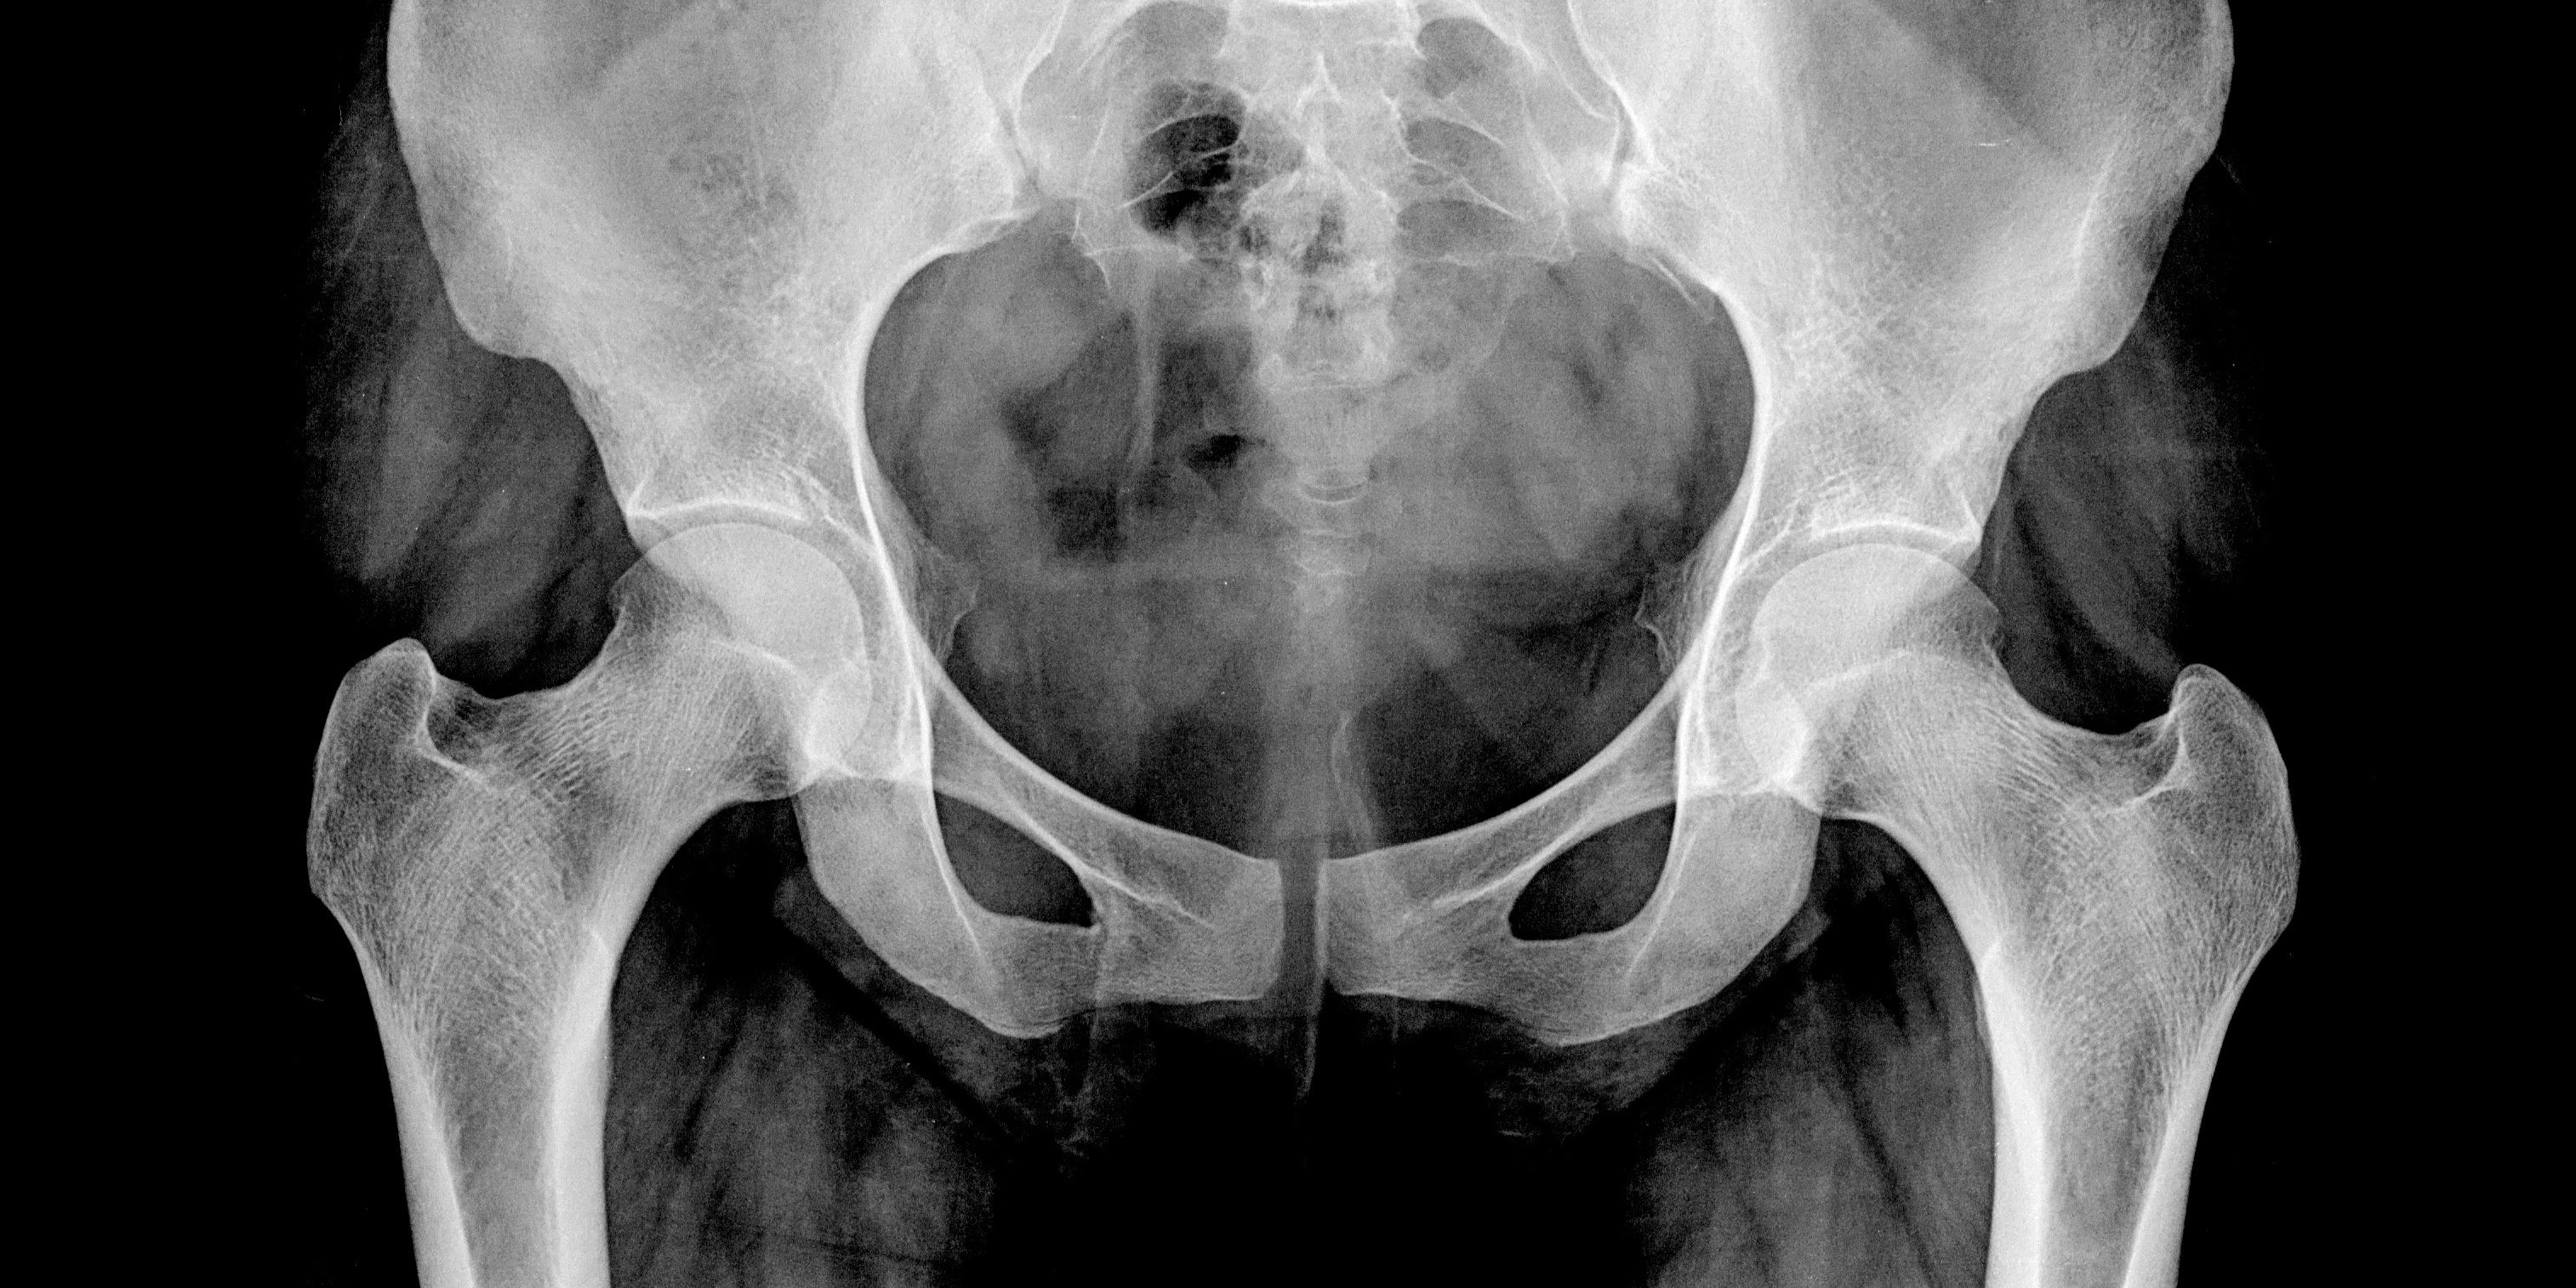

Sporters met terugkerende liesklachten checken we op rompinstabiliteit of een blokkade in de onderrug of het bekkengebied. Ook kunnen liesproblemen worden teruggebracht tot heupslijtage en artrose.